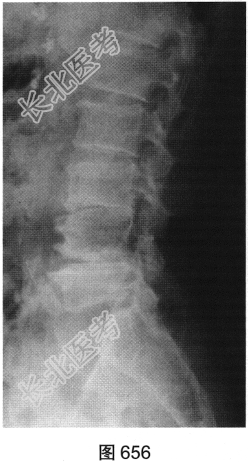

- 多项选择题2.[提示]患者行腰椎X线及CT检查,见图655~图659。患者有哪些阳性影像学表现( )

A、椎间盘“真空现象”

B、腰椎前滑脱

C、椎间盘膨出、突出

D、腰椎轻度侧弯

E、椎小关节骨质增生硬化

F、腰椎间隙变窄